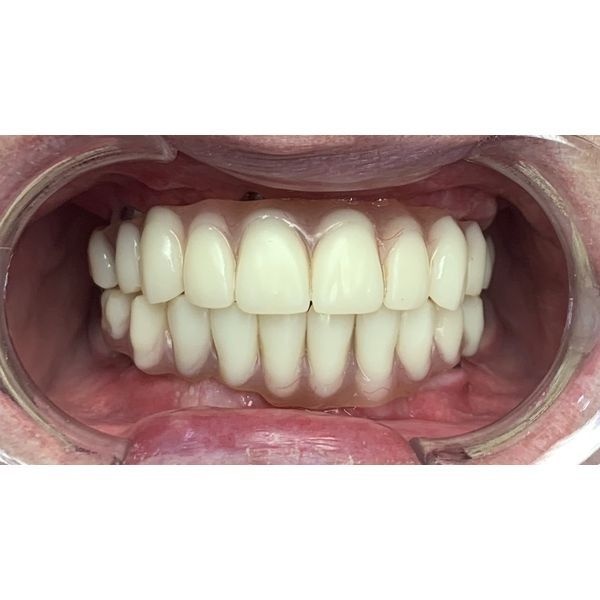

Полгода женщина носила временную конструкцию. За это время она дважды делала контрольные ортопантомографические снимки и компьютерную томографию, чтобы контролировать состояние полости рта. Когда импланты прижились, ей поставили постоянный протез.

Результат лечения полностью удовлетворил пациентку: она избавилась от проблем с дикцией, перестала ограничивать себя в еде и стала более уверенной. Теперь каждые полгода женщина приходит на профилактический осмотр и гигиену полости рта.